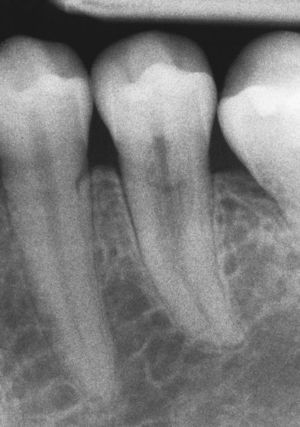

Características radiográficasDesde el punto de vista radiográfico, las reabsorciones externas (fig. 6) se caracterizan por los siguientes signos:

Luz del conducto radicular no dilatada.

Imagen radiolúcida en la zona radicular de límites irregulares.

Localización asimétrica.

La localización cambia con la proyección radiológica excéntrica.

Desaparición localizada del espacio periodontal.

En primer lugar se ha de evaluar la conveniencia de conservar el diente afectado. Con frecuencia el diagnóstico no se establece en el estadio inicial, sino con un retraso considerable, lo que favorece la expansión de la lesión y el debilitamiento de la sección de la raíz. Se ha de determinar la ubicación de la reabsorción en el perímetro del diente y se ha de evaluar la accesibilidad quirúrgica de la lesión8. En caso de duda se puede recurrir a la tomografía volumétrica digital para obtener información sobre la localización y la extensión horizontal del defecto de reabsorción y de la sección residual de la raíz2,15.